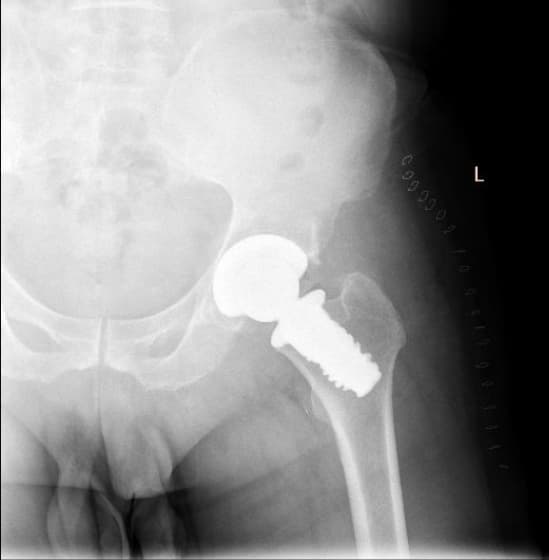

Түнхний толгой хэсгийн цусан хангамжийн алдагдалын улмаас үхжилт өөрчлөлттэй өвчтөний мэс заслын өмнөх болон дараах рентген зураг

Түнхний үе бүтэн солих мэс засал (THA) image1Түнхний үе бүтэн солих мэс засал (THA) image2